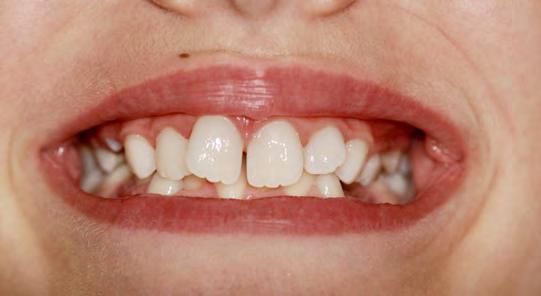

Presentazione del caso > F.V, bambino di cinque anni, presenta una malocclusione di II Classe scheletrica, III Classe dentale molare e canina destra e sinistra, morso inverso anteriore. Le arcate dentali mostrano usura degli elementi dentari anteriori a causa dell’occlusione patologica. Le linee mediane, superiore ed inferiore, sono centrate; il frenulo labiale superiore patologico per un’eccessiva estensione inter-incisale.

Dall’esame clinico si evince la III Classe dentale, l’inversione anteriore e l’over-jet negativo.